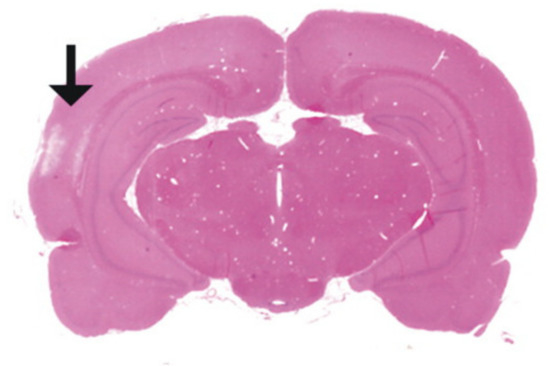

- Bramlett, H.M.; Dietrich, W.D. Quantitative structural changes in white and gray matter 1 year following traumatic brain injury in rats. Acta Neuropathol. 2002, 103, 607–614. [Google Scholar] [CrossRef] [PubMed]